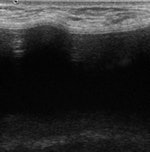

Conventional breast imaging techniques, especially ultrasound, still provide useful information about implants. However, intracapsular rupture, which is frequent but often clinically silent, cannot be easily detected by mammography because of the radiopacity of the implant. The sensitivity of ultrasound is greater if discontinuous echogenic lines within silicone gel ("stepladder sign") are detected. Periprosthetic hyperdensity on mammography and the "snowstorm sign" on ultrasonography are significantly associated with extracapsular rupture.